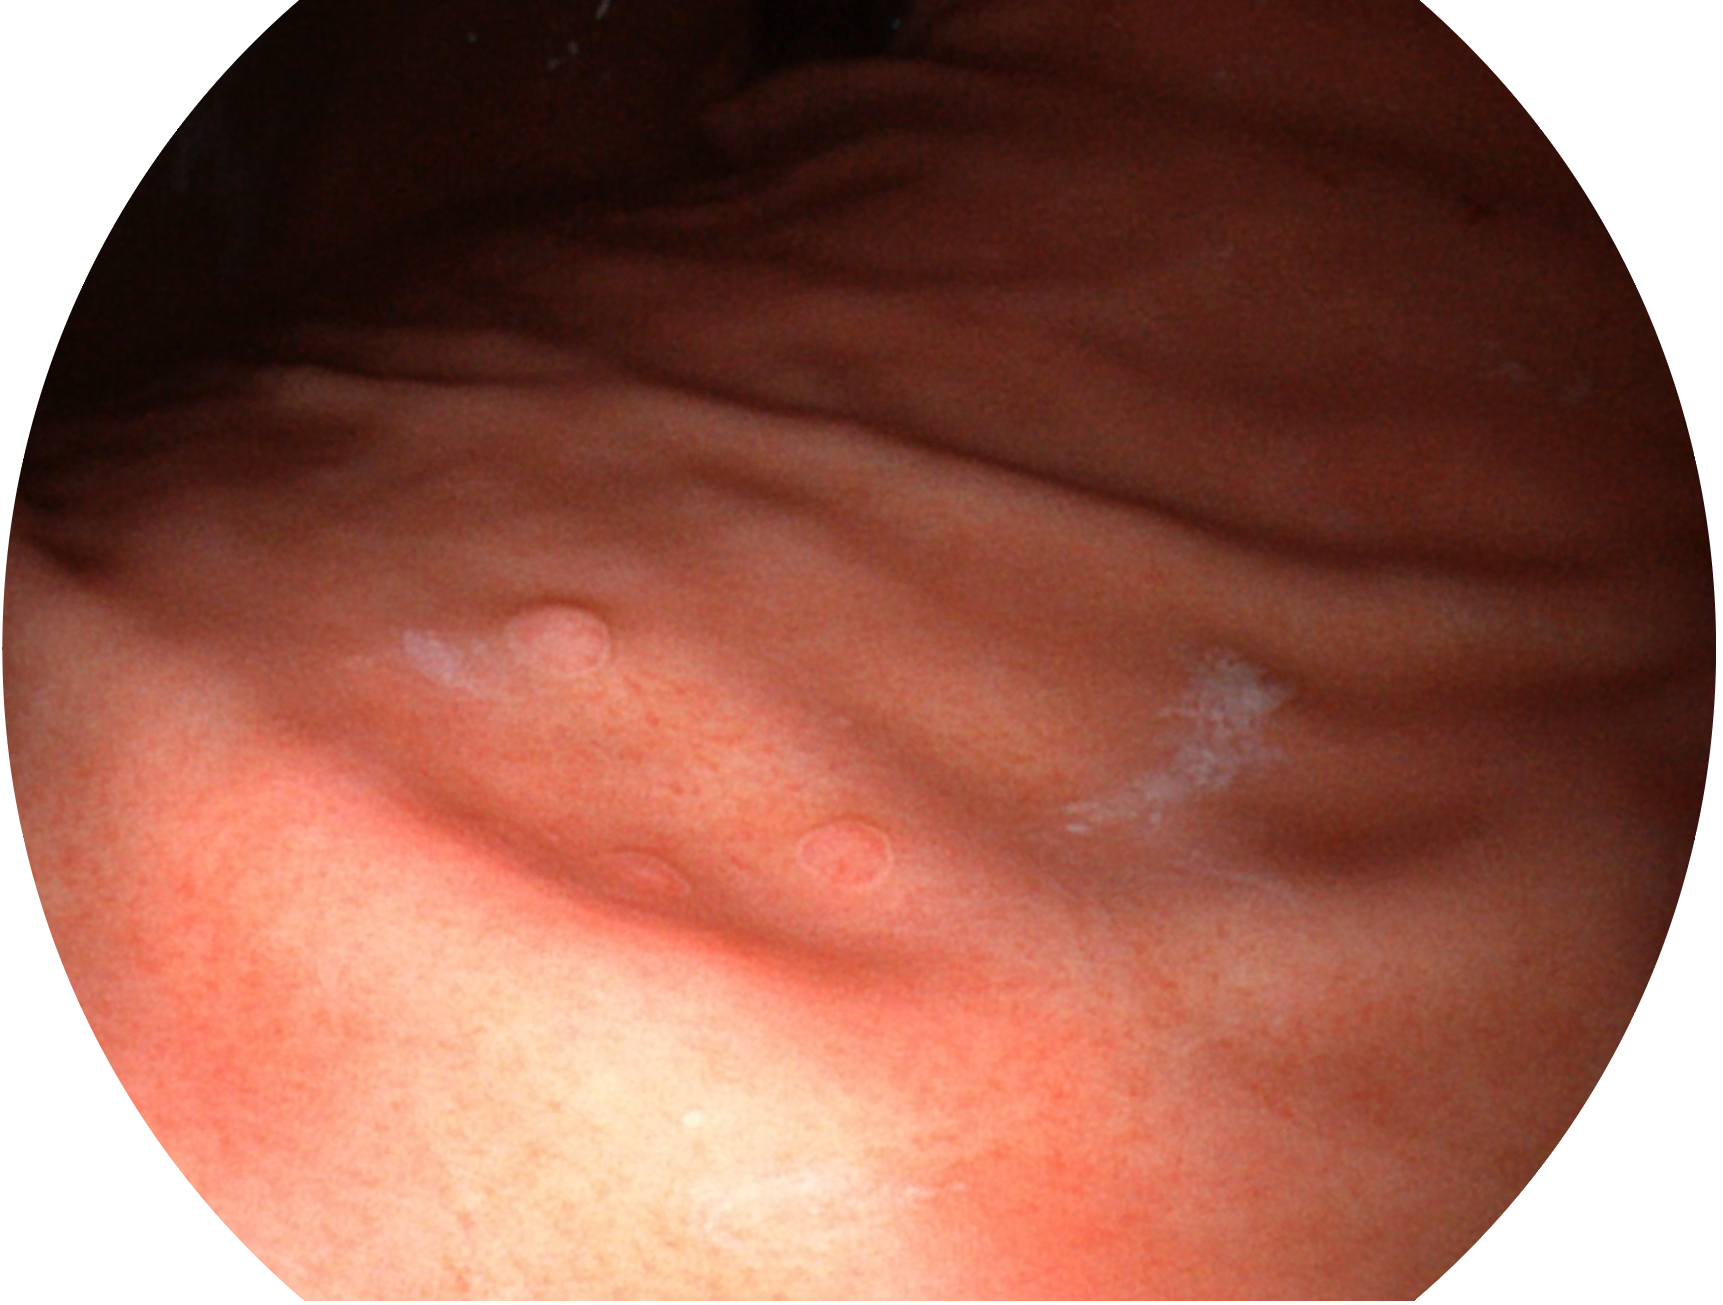

银河集团官网新开发的内镜染色技术,主要是基于多波长LED 光源的开发,VLS-55Q 四波长LED 光源是由四个不同颜色的LED光按照相应照明模式所规定的特定发光比例进行合束后形成,合束后形成的照明光的光谱由红光、绿光、蓝光及蓝紫光这四个不同的波段范围构成。具有更高光谱自由度,通过光谱比例的控制,实现了聚谱成像技术,英文全称为“Spectral Focused Imaging, SFI”,缩写为“SFI”和光电复合染色成像技术,英文全称为“Versatile Intelligent Staining Technology, VIST”,缩写为“VIST”。